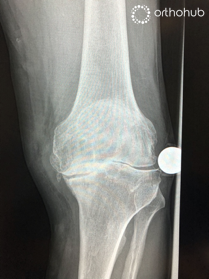

This is a 68 year old man has significant pain in his knee and has failed conservative treatment. He has no significant co-morbities.

On examination there is varus deformity with fixed flexion. Neurovascular examination is normal.